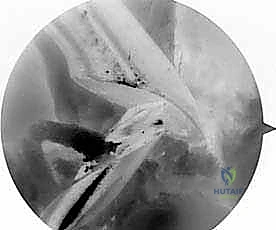

- الجراحة المجهرية وتنظير المفاصل بدقة 4K: يستخدم الدكتور هطيف أحدث تقنيات مناظير الركبة (Arthroscopy) المزودة بكاميرات عالية الدقة 4K، مما يتيح له رؤية أدق التفاصيل داخل المفصل، وتشخيص الأضرار المجهرية، وإجراء الجراحة بأقل تدخل جراحي ممكن (Minimally Invasive).

* التصوير بالرنين المغناطيسي (MRI): يوفر صورة مفصلة للأنسجة الرخوة. يحدد حالة الطعم المزروع سابقاً (هل هو ممزق، متآكل، أم سليم ولكنه غير فعال؟)، ويقيم حالة الغضاريف الهلالية والمفصلية.